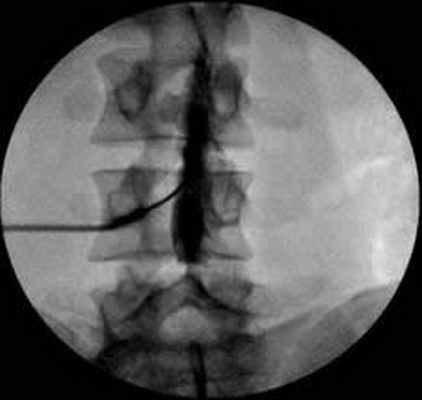

Прогрессирующая некротическая миелопатия

Прогрессирующая некротическая миелопатия, которая сочетает в себе невыраженное воспаление, встречается в качестве отдаленного эффекта рака при солидных опухолях. Миелографическая картина и спинномозговая жидкость (СМЖ, ликвор) обычно нормальные, с незначительным повышением уровня белка. Подострый прогрессирующий спастический парапарез развивается у больных в течение нескольких дней или недель и обычно характеризуется асимметричностью. Этому сопутствуют парестезии в дистальных отделах конечностей, распространяющиеся вверх до формирования уровня чувствительных расстройств, и позднее — нарушение функции тазовых органов (дисфункция мочевого пузыря). При прогрессирующей некротической миелопатии поражаются также несколько соседних сегментов спинного мозга.

Контрастное вещество, видимое при миелографии, вводится в субдуральное пространство посредством люмбальной пункции.